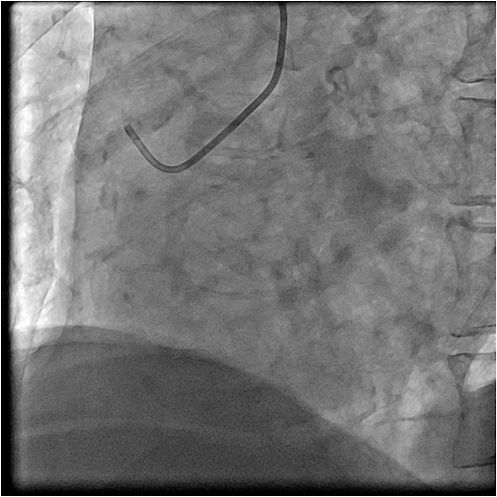

急诊PCI-左冠

急诊PCI--右冠

左冠植入支架

支架植入后